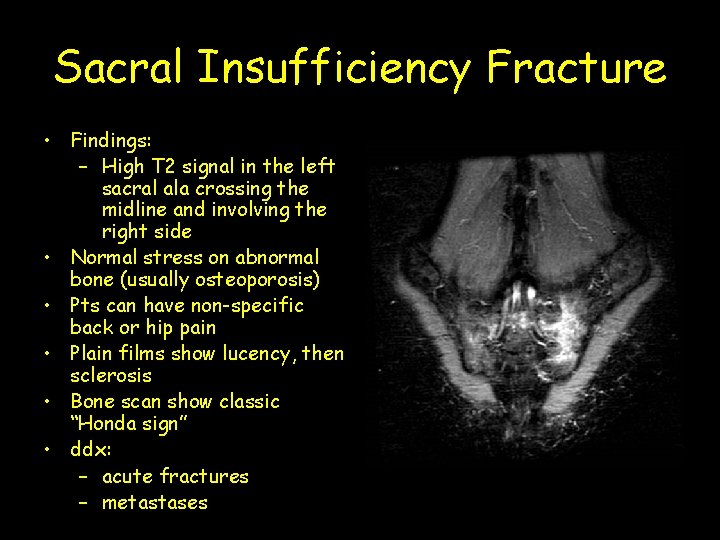

Sacral Insufficiency Fracture • Findings: – High T 2 signal in the left sacral ala crossing the midline and involving the right side • Normal stress on abnormal bone (usually osteoporosis) • Pts can have non-specific back or hip pain • Plain films show lucency, then sclerosis • Bone scan show classic “Honda sign” • ddx: – acute fractures – metastases